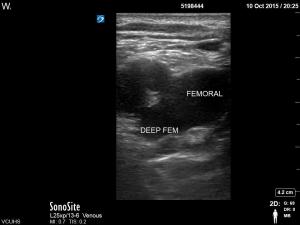

D. Clip of Femoral Vein joining Deep Femoral Vein with compression